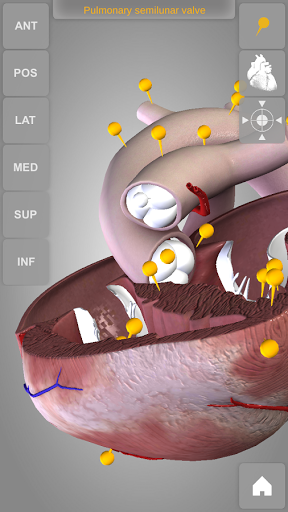

Heart 3D Atlas of Anatomy allows you to rotate a highly realistic 3D heart model as it was in your hands.

The human heart anatomical 3D model is revolvable in any direction giving a 360° view of the object.

User can choose external view or section view. Moreover, the names of specific anatomical areas can be shown touching the related pins (available in the full version only).

Heart app is part of 3D Atlas of Anatomy collection, a human anatomy reference atlas for tablet and smartphone devices. The 3D medical models in these apps are similar to classic real plastic models but with the great benefits to be always available on your portable devices when you need them and occupy no physical space.

These apps can be of great help for students of medicine or to anyone who needs to study human anatomy shape in detail and from any angle. Immediacy and simplicity together with high quality are distinctive features of the app.